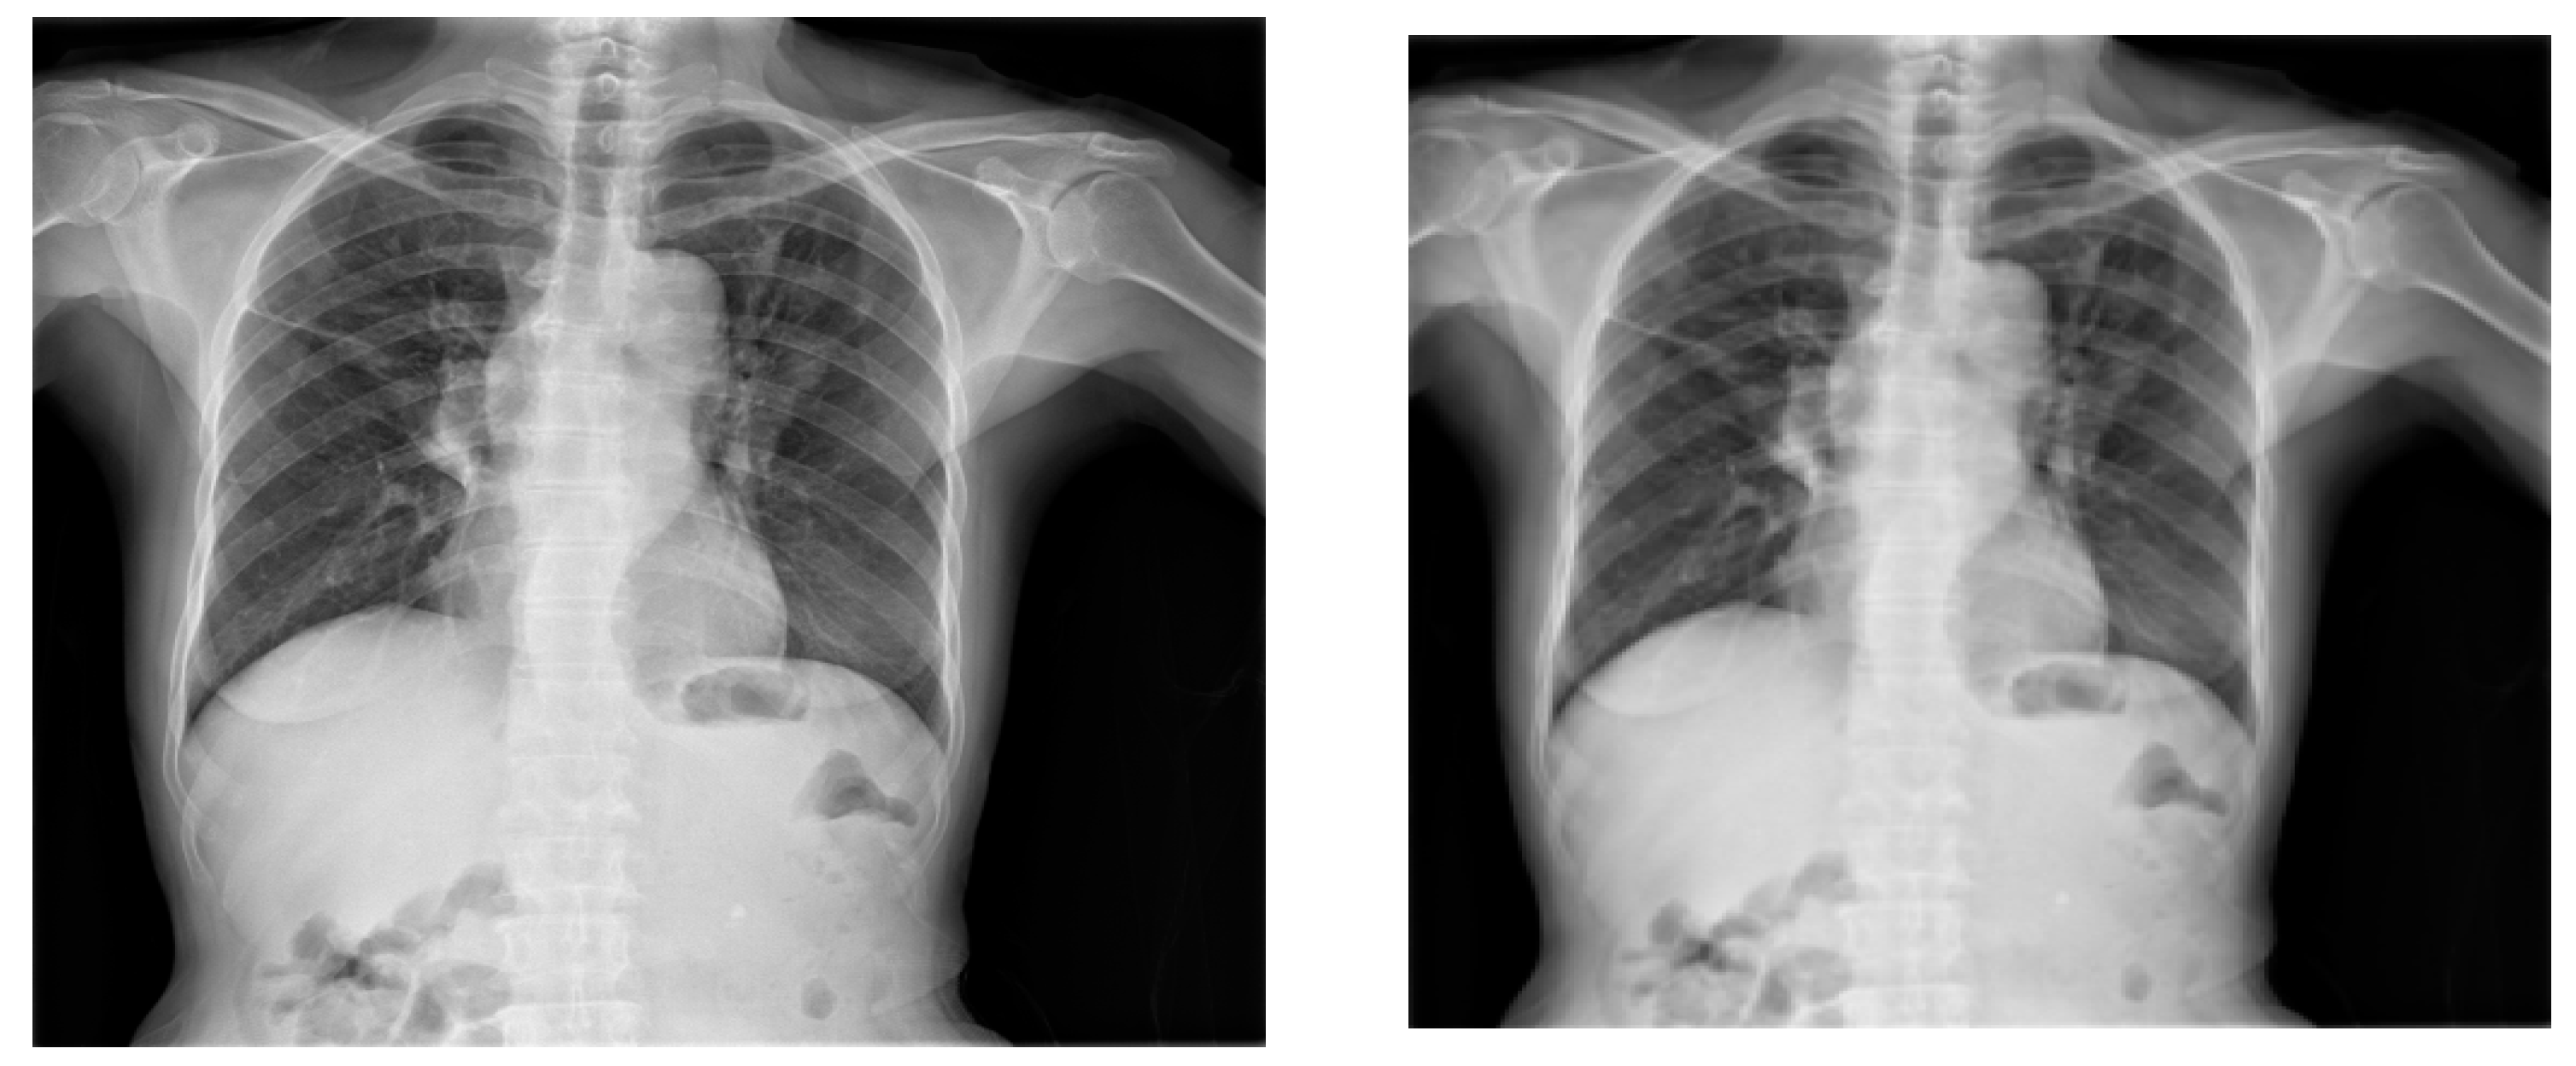

Similarly, scaling is also a frequently employed augmentation technique, as illustrated in Figure 7. To implement a scaling transformation with a scaling factor of 0.8, the Image library was utilized. This involved adjusting the size of the X-ray image uniformly to 80% of its original dimensions. Notably, the scaling transformation was extended to maintain consistency within the corresponding bounding box; a process seamlessly executed using the Image library. This ensures that the scaling effect persists coherently across both the X-ray image and its associated bounding box.

Figure 7. Original X-ray (left) and 0.8 scaled X-ray (right).

Information 14 00655 g007

Figure 8. Original X-ray (left) and horizontal flipping of the X-ray (right).

Information 14 00655 g008